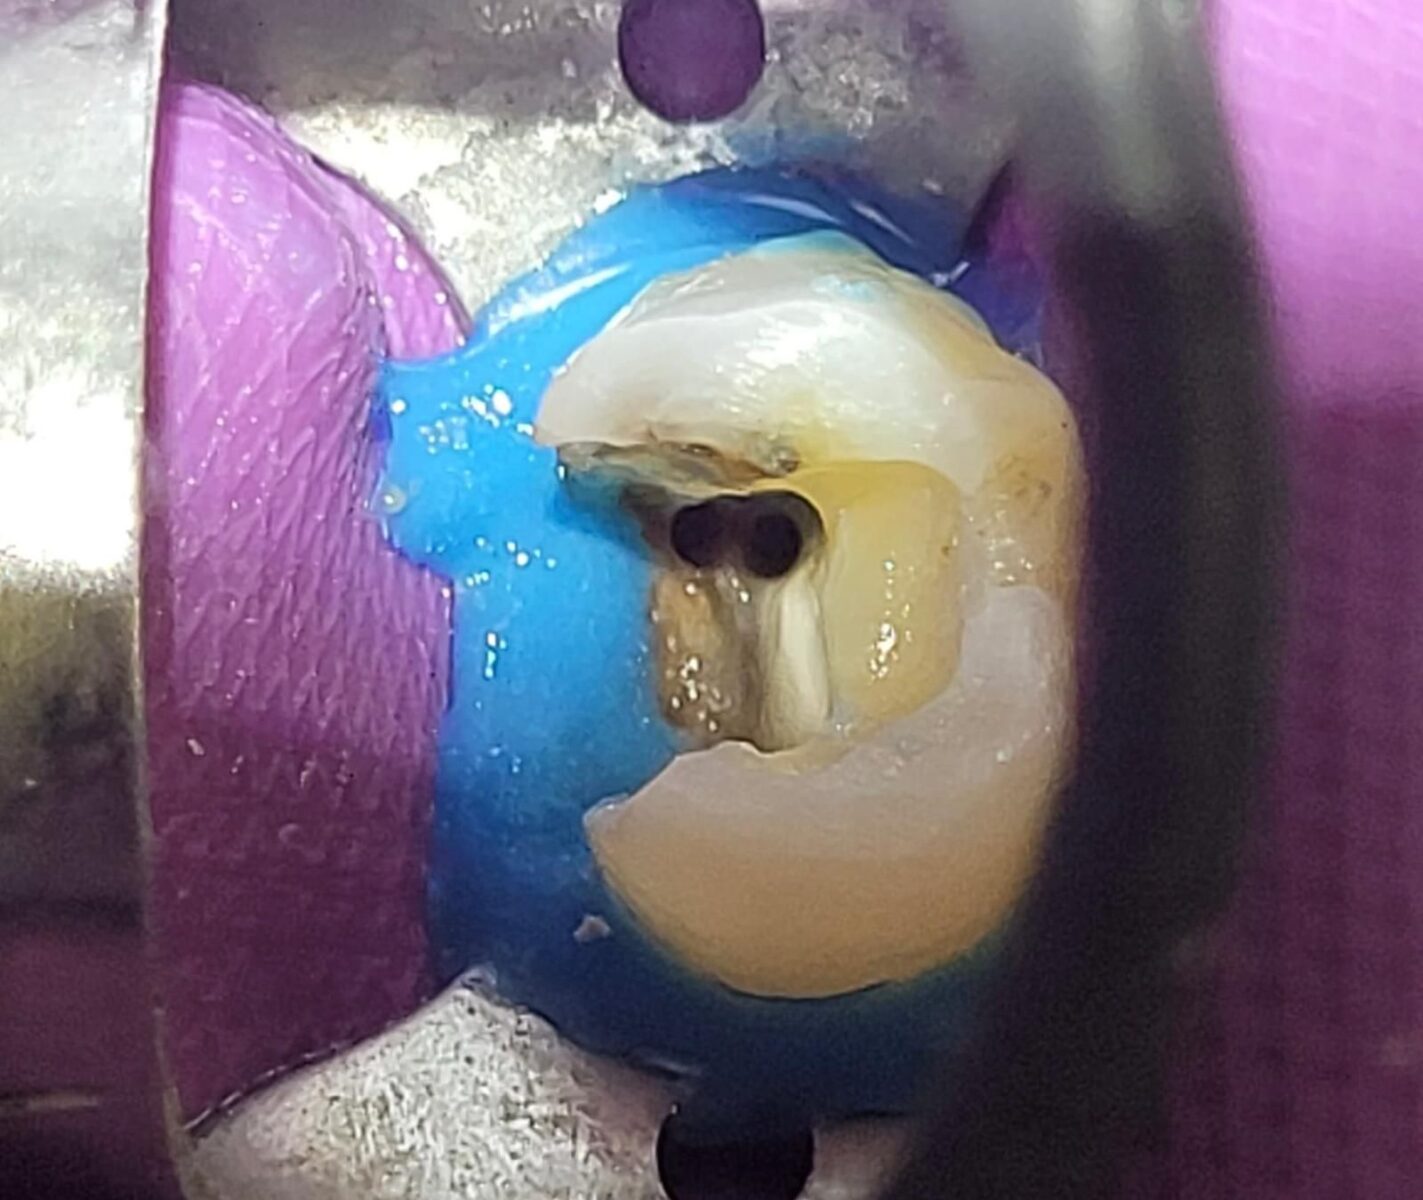

- Designing a precise access cavity that would allow reliable location and negotiation of the complex multi-canal system, all while maximizing the preservation of remaining healthy tooth structure after complete removal of extensive decay.

- Safely negotiating and managing a highly intricate, molar-like canal network within the inherently more restricted anatomical dimensions of a premolar root.

Adequate access was essential—not only to locate and negotiate the canal system but also to do so while conserving as much tooth structure as possible. Once the decay was fully removed and access achieved, shaping was carried out using the DENCO Chameleon Dual Shaper. This instrument allowed for conservative and controlled preparation, effectively preserving the original canal anatomy and minimizing excessive dentin removal. Respecting the internal morphology throughout the procedure was key to maintaining canal integrity.